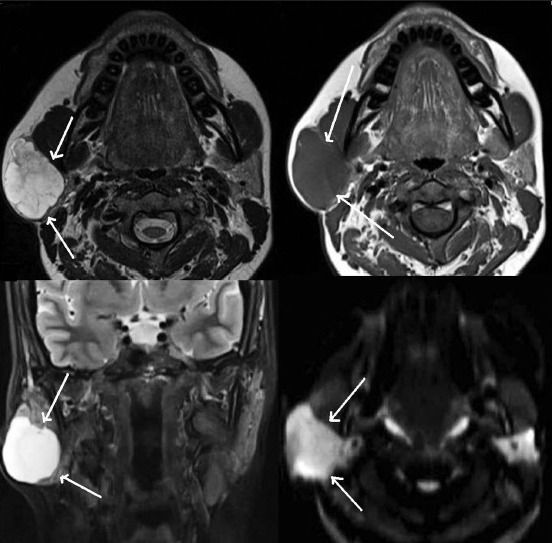

(Слева) МРТ Т1ВИ FS c КУ, аксиальная проекция. Ребенок с рецидивирующим паротитом. Левая железа увеличена в размерах и интенсивно накапливает контрастное вещество. Значительного воспаления жировой клетчатки нет. Обратите внимание, что в добавочной железистой ткани также происходит умеренное накопление контраста.

(Справа) Сиалограмма в боковой проекции, этот же пациент. В левой железе определяются множественные небольшие капли/скопления контраста, также они имеются и в добавочной железе. Обратите внимание, что размер протоков остается нормальным.

(Справа) MPT Т2ВИ FS, аксиальная проекция. Двустороннее увеличение околоушных желез, имеются многочисленные участки усиления сигнала. Пациент с обострением аутоиммунного сиалоаденита. Обратите внимание, что процесс диффузный и захватывает глубокие доли желез.

3. МРТ при остром паротите:

• Т2ВИ:

о Диффузный гиперинтенсивный сигнал ± локальные участки сигнала повышенной интенсивности (микроабсцессы или расширение протоков)

• Т1ВИ с КУ:

о Увеличенная околоушная железа, равномерно неинтенсивно накапливающая контрастное вещество

о Абсцесс: скопление жидкости с периферическим кольцом накопления контраста